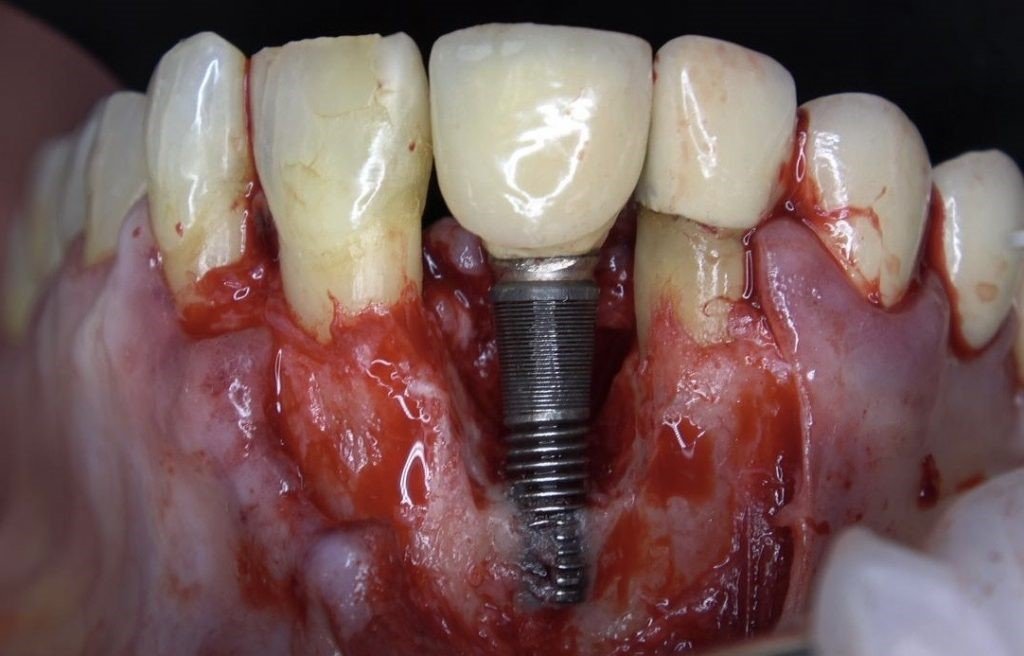

Phase 2: Surgical Therapy

- Access Flap Surgery:

- Full-thickness mucoperiosteal flap elevated

- Complete granulation tissue removal

- Thorough implant surface decontamination:

- Mechanical: titanium brushes

- Chemical: 3% hydrogen peroxide followed by saline irrigation

- Laser decontamination: Er:YAG laser (100mJ/pulse, 10Hz)

- Regenerative Procedure:

- Defect morphology assessment revealed a contained circumferential defect

- Application of enamel matrix derivative (Emdogain®)

- Grafting with particulate xenograft (Bio-Oss®) mixed with autogenous bone chips harvested from adjacent area

- Coverage with resorbable collagen membrane (Bio-Gide®)

- Tension-free primary closure with 5-0 PTFE sutures